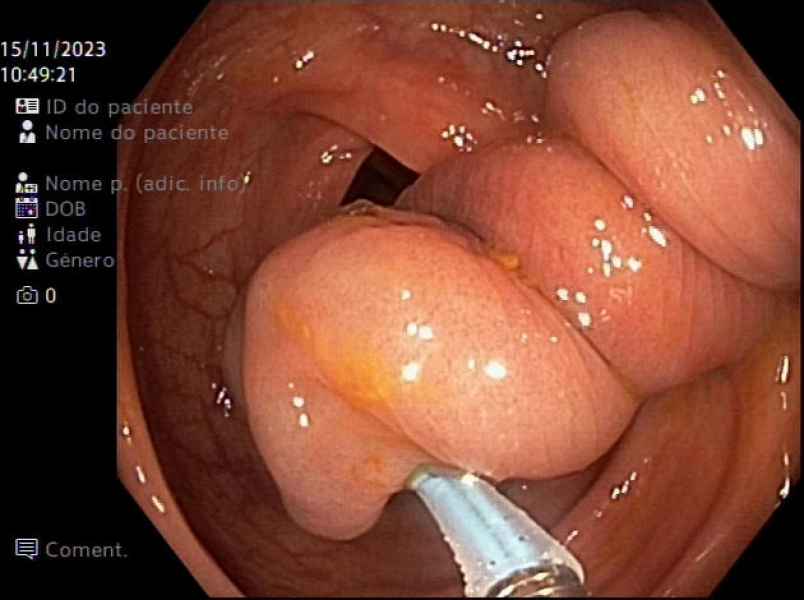

Advancing Care for Juvenile Peutz-Jeghers Syndrome

Fotografia